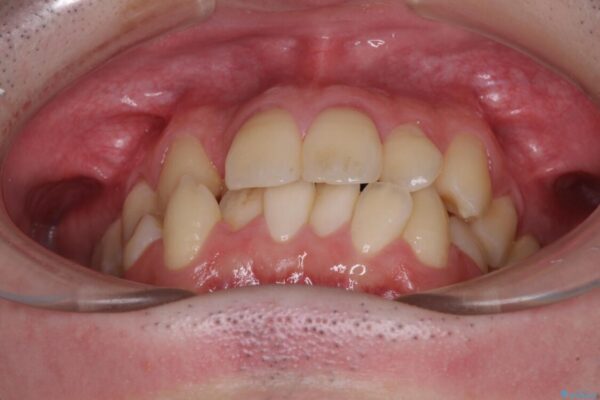

治療前

• 全顎的なクロスバイト 補助装置を用いてワイヤー矯正 治療前画像